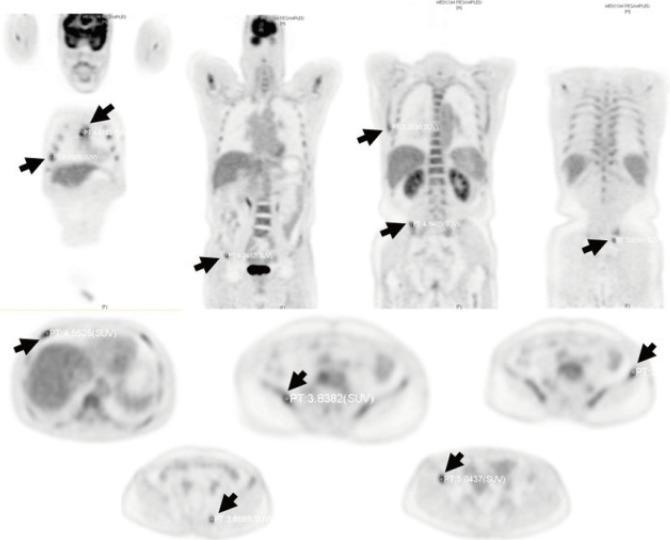

多发性骨髓瘤酷似直肠腺癌骨转移。

Multiple Myeloma Mimics Bone Metastasis From a Rectal Adenocarcinoma.

A presumptive diagnosis of bone metastasis can be easily made when a patient with a history of colorectal cancer develops bone lesions that are seen on follow-up imaging. In this case report, we describe a patient whose multiple bone lesions were wrongly attributed to a recurrence of rectal cancer rather than being identified as multiple myeloma lesions. When clinicians detect new, abnormal, bony lesions in a patient with a previous history of cancer, they should consider diseases such as multiple myeloma in their differential diagnosis.

摘要

当一名有结直肠癌病史的患者出现后续影像学检查可见的骨病变时,骨转移的初步诊断很容易做出。在本病例报告中,我们描述了一名患者,其多处骨病变被错误地归因于直肠癌复发,而未被识别为多发性骨髓瘤病变。当临床医生在有癌症病史的患者中检测到新的、异常的骨病变时,在鉴别诊断中应考虑诸如多发性骨髓瘤等疾病。